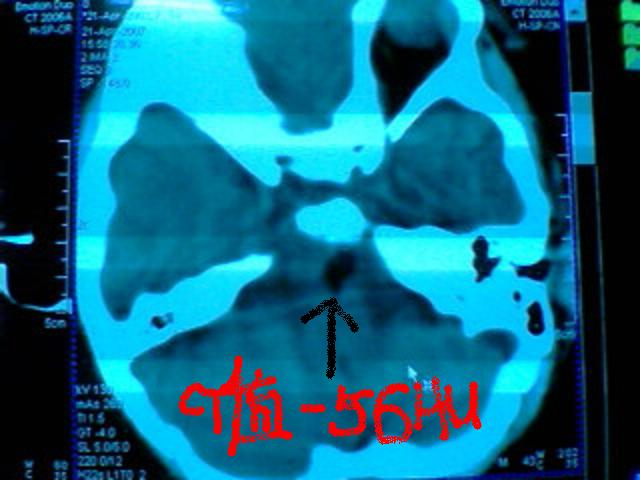

发热2天 无咳嗽咳痰 抽搐数次 现浅昏迷

脂肪瘤?皮样囊肿?表皮样囊肿?

请测一下眶内脂肪及脑脊液的密度值

考虑 脑干脂肪瘤可能性大

基底池脂肪瘤。

考虑:左侧桥小脑角池、基底池表皮样囊肿可能性大。

左侧桥小脑角池表皮样囊肿可能性大,部分突入桥前池,引起脑干受压